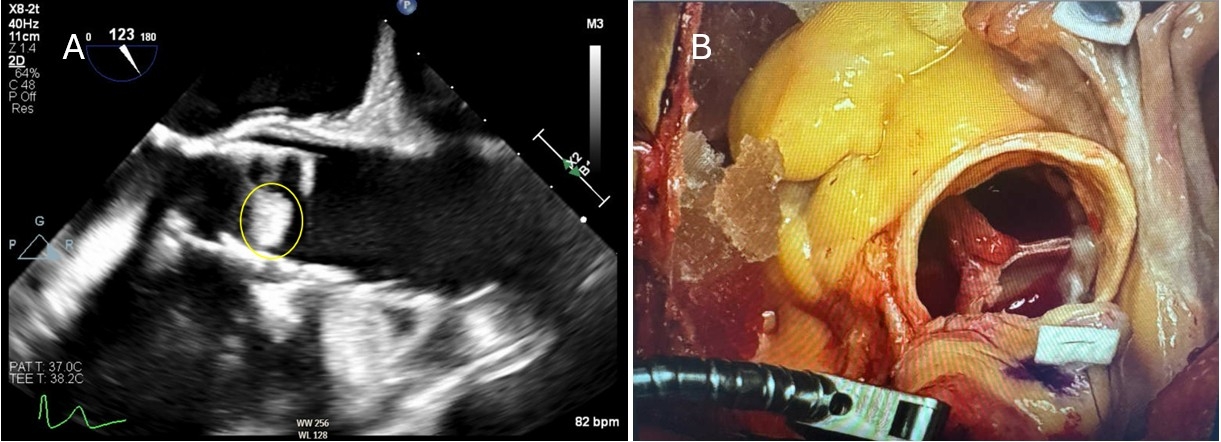

A 70-year-old man with a remote history of lymphoma (treated with abdominal tumor resection and radiation) and severe aortic stenosis status post-TAVR presented with a 1.2 cm vegetation on the bioprosthetic valve. One month prior, he had Gemella bacteremia, treated with IV vancomycin and oral minocycline. Although clinically improved, repeat transesophageal echocardiography (TEE) revealed a new valve vegetation (Figure 1A). Blood cultures were negative, and he remained afebrile and hemodynamically stable. He denied recent dental work. Maxillofacial CT showed no dental infection. Abdominal imaging revealed a stable soft tissue mass in the posterior mediastinum, consistent with residual changes from his prior lymphoma. His abdominal surgery and radiation likely led to long-term mucosal barrier injury, predisposing to translocation of Gemella, a GI tract commensal. With recent bacteremia, a new valve vegetation, and a prosthetic valve, PVE was diagnosed. He received six weeks of IV vancomycin and ultimately underwent surgical TAVR explant and valve replacement (Figure 1B).